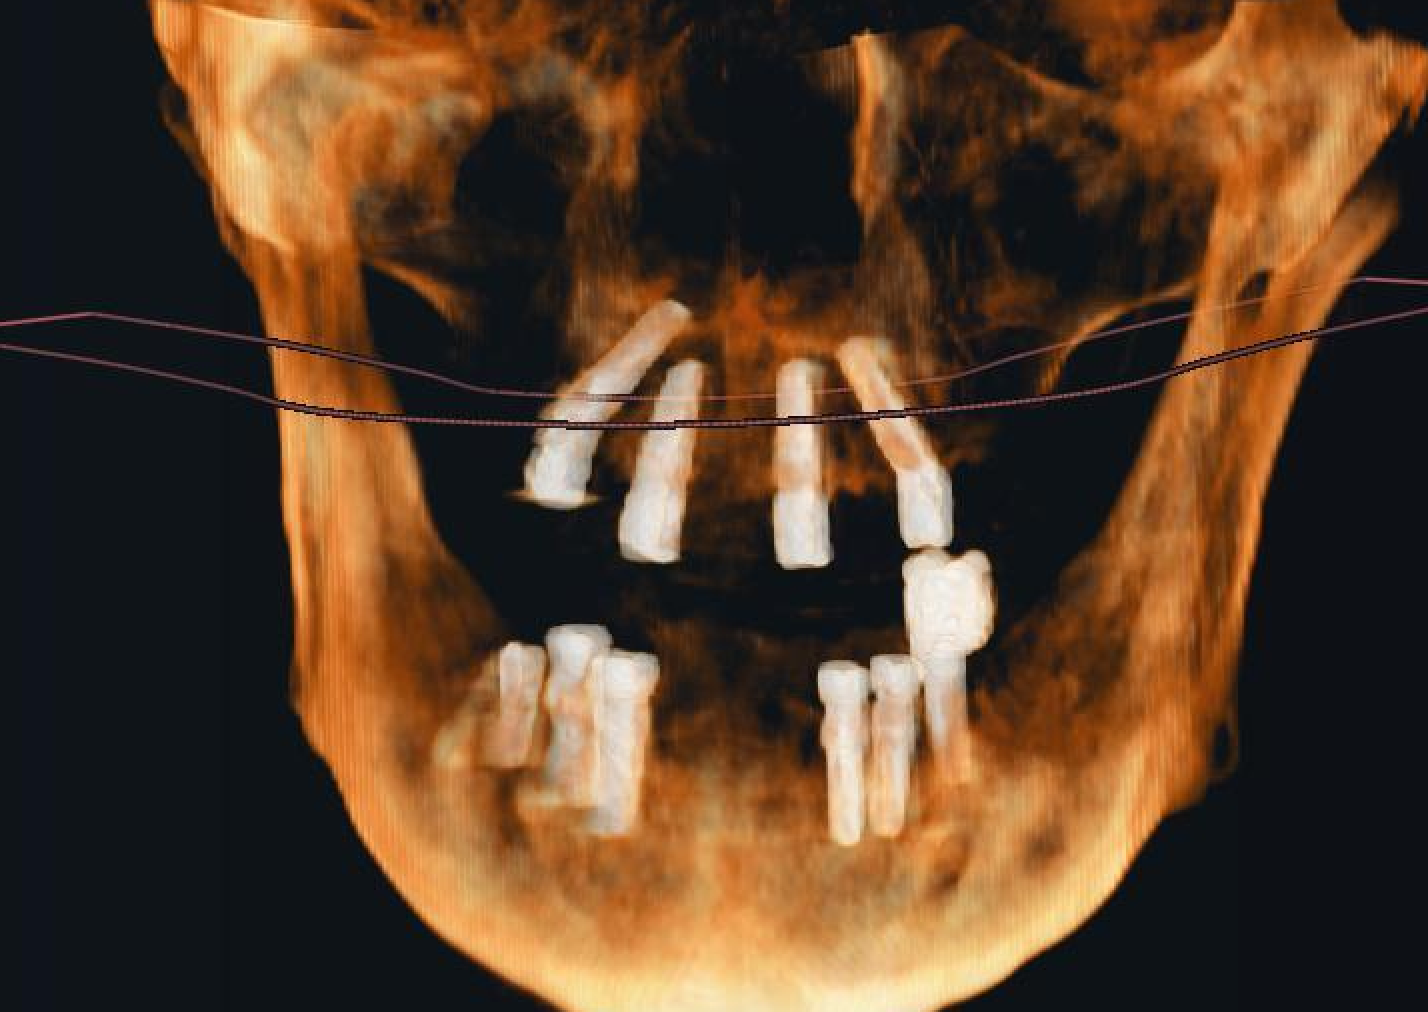

Sinus Avoidance Technique: Placement of 4 Upper Jaw and 6 Lower Jaw Implants

In cases where sinus augmentation procedures are not feasible or preferred, alternative techniques must be employed to ensure successful implant placement in the upper jaw. This case presentation discusses the utilization of a sinus avoidance technique for the placement of 4 implants in the upper jaw and 6 implants in…